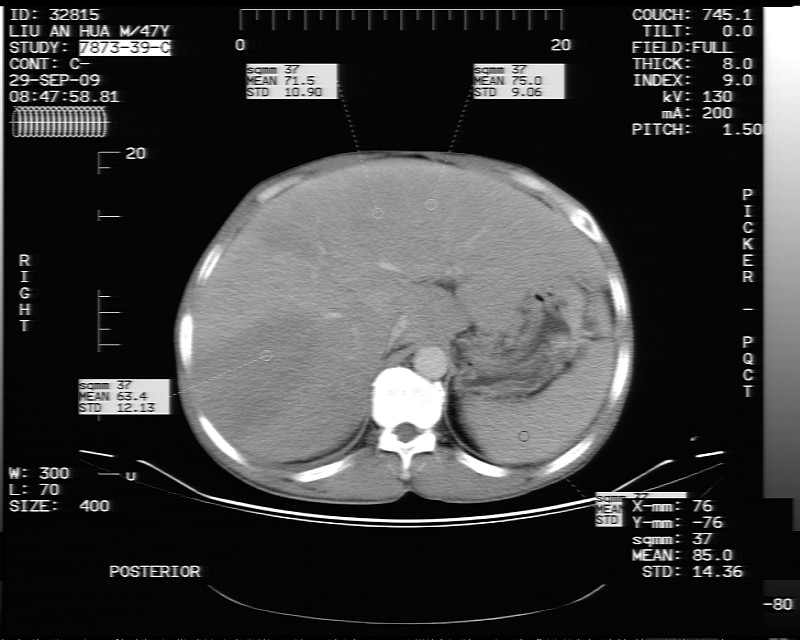

动态增强示:

支持脂肪肝【无占位性,高低密度区同期强化,平扫与强化的密度成比例】

不均匀性脂肪肝。肝脏体积稍大,不除外合并肝功能损害。

1、不均匀脂肪肝;2、布加氏综合症(肝脏肿大,门脉纤细,下腔海绵状变性,肠系膜上静脉显著扩张)。